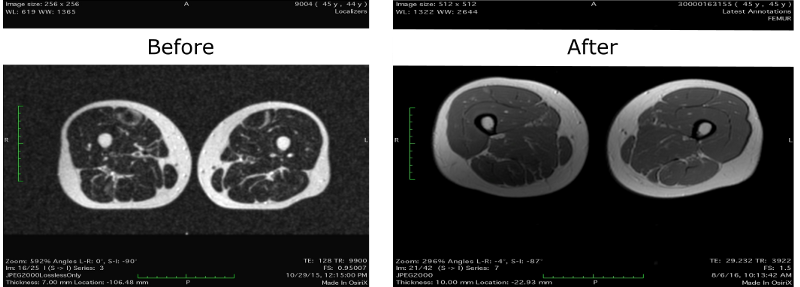

Там она утверждает, что данные МРТ её бедер показывают снижение “мраморности” мышц, то есть снижение количества внутримышечных жировых отложений, что может быть расценено как положительный эффект от фоллистатиновой терапии:

Но, возможно, визуальная разница между снимками обусловлена лишь улучшением разрешения МРТ: старый снимок был сделан на аппарате в 1 Тесла, а новый — 1,5 Тесла. Кроме того, мне кажется, что изображения получены из немного разных мест в бедрах — более свежие изображения, судя по расстоянию между ногами, взяты со срезов чуть ниже от таза, чем старые. А чем ниже от попы, тем меньше процент жира в ногах. Хотя, может, Лиз просто чуть шире расставила ноги в последнем тесте.